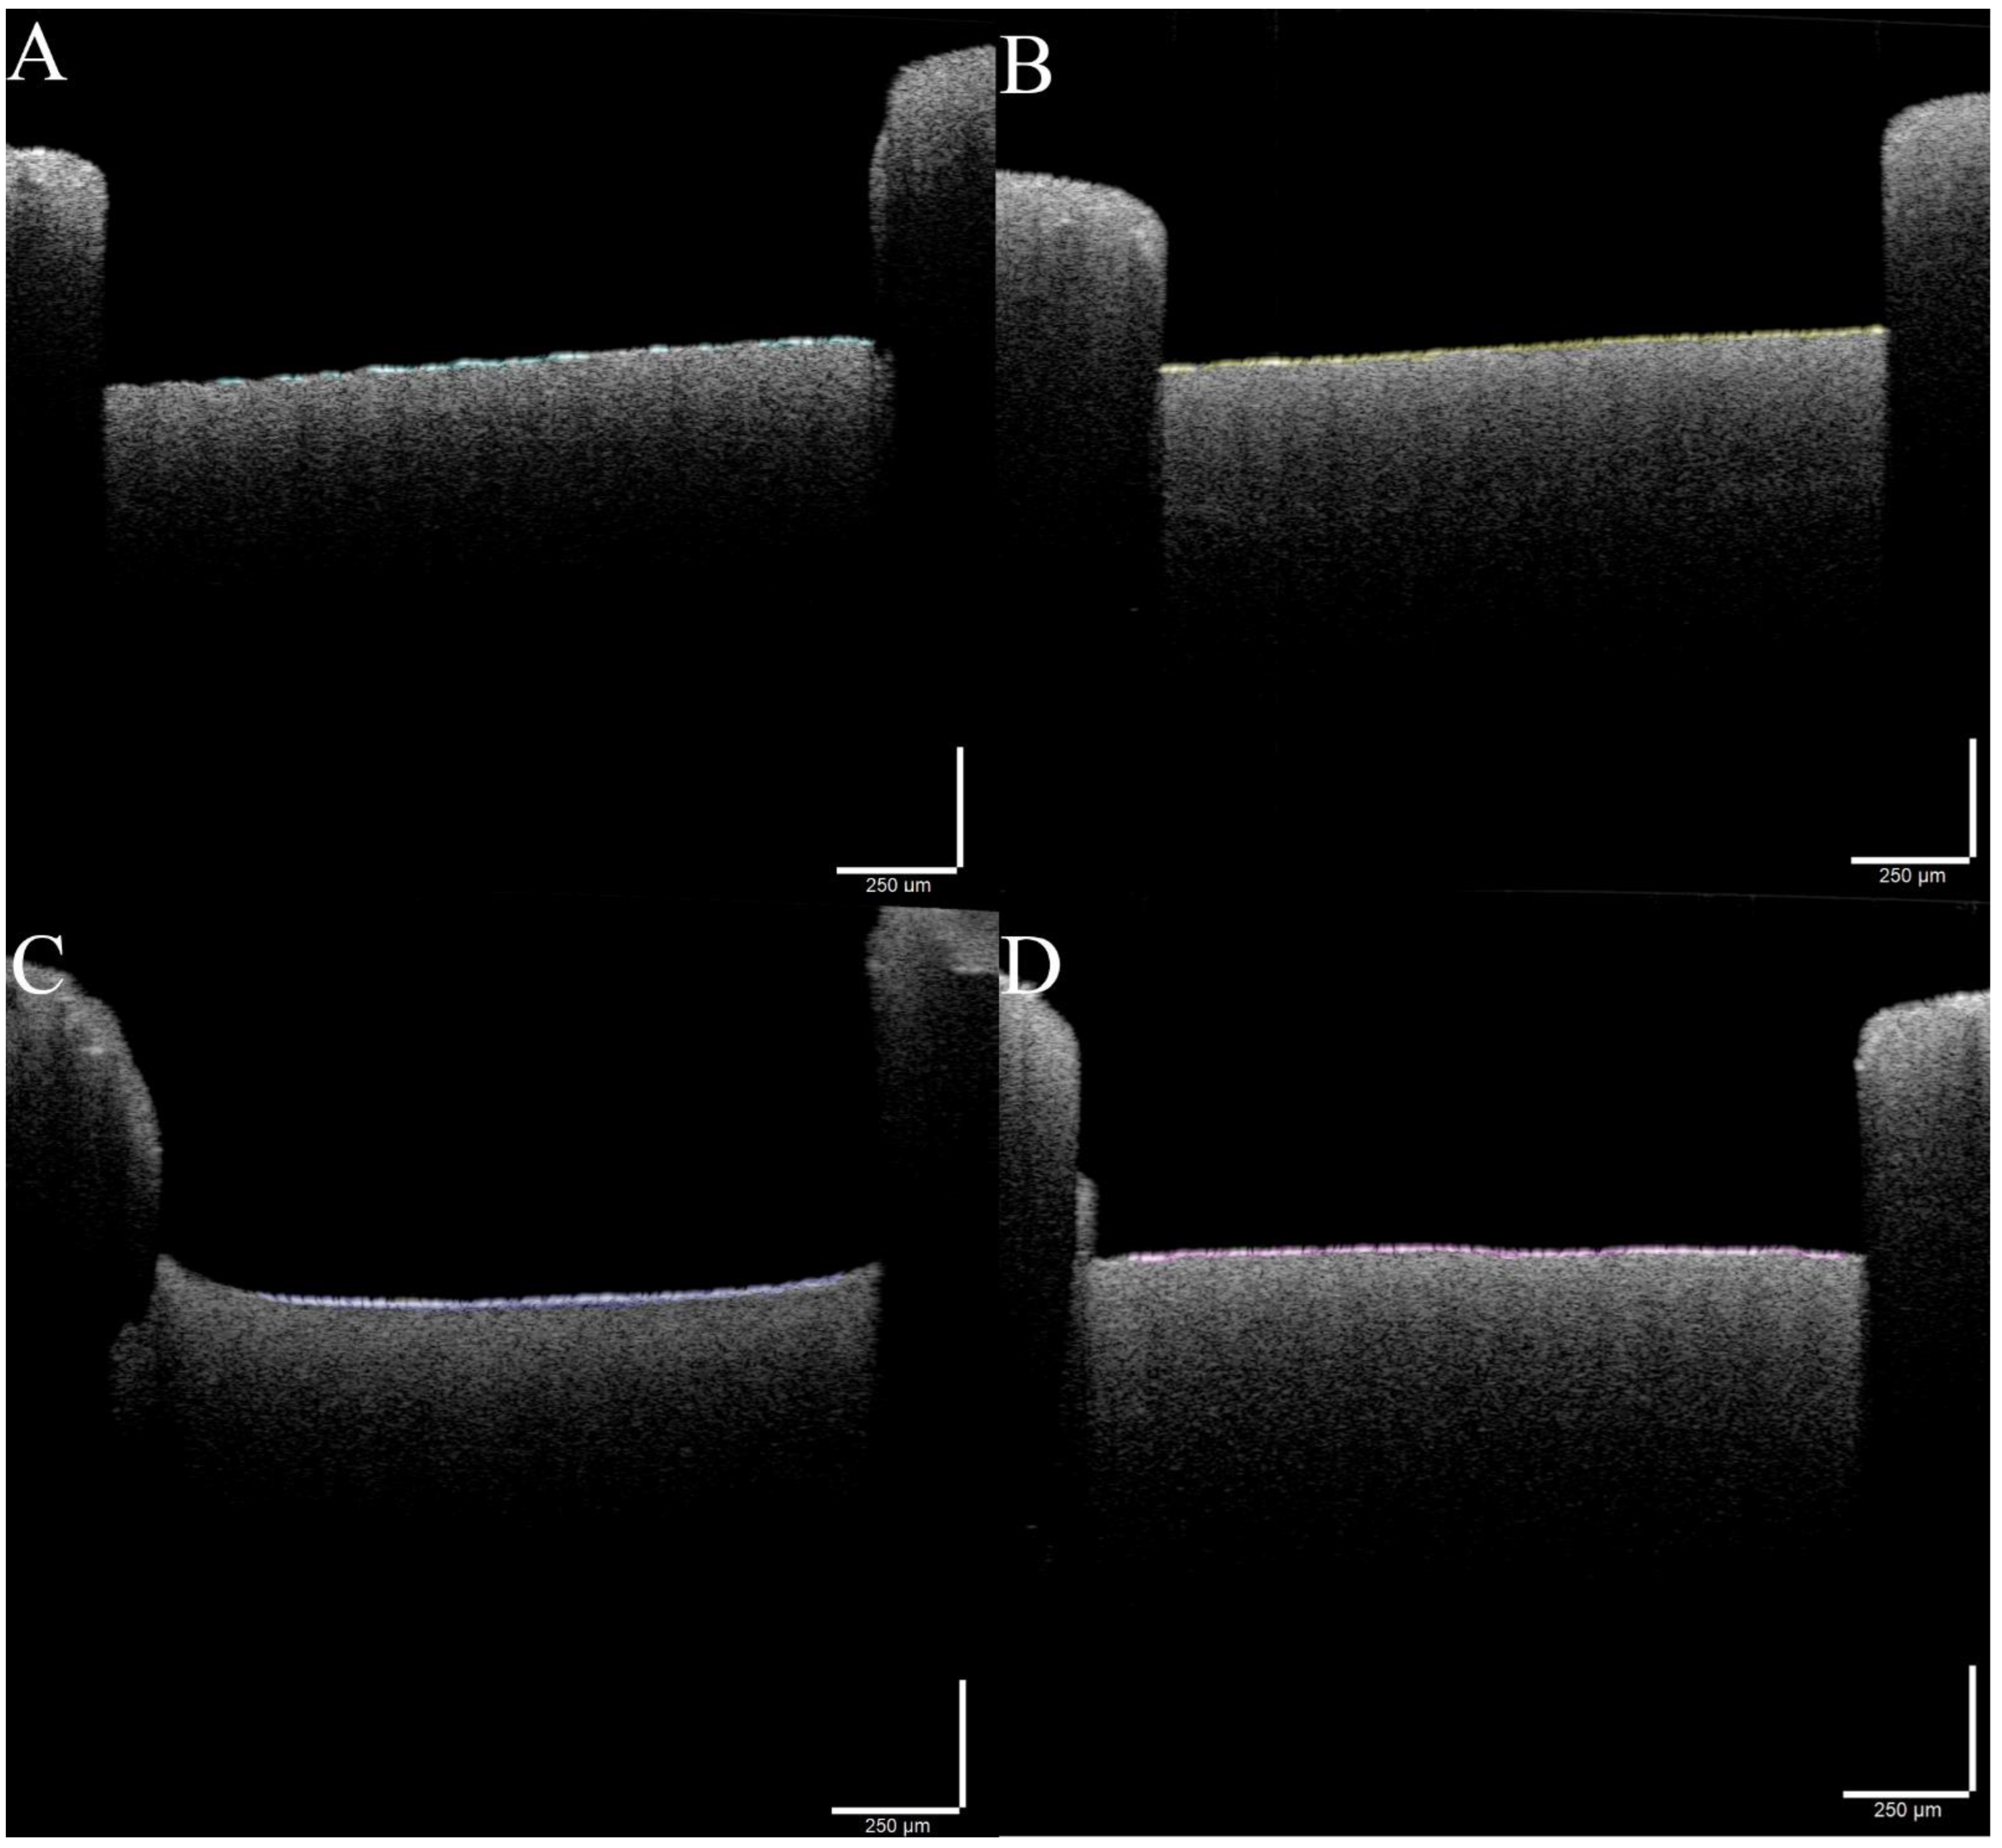

2.3.2. Optical Coherence Tomography (OCT), Scanning Electron Microscopy (SEM) and Fourier Transform Infrared (FTIR) Spectroscopy